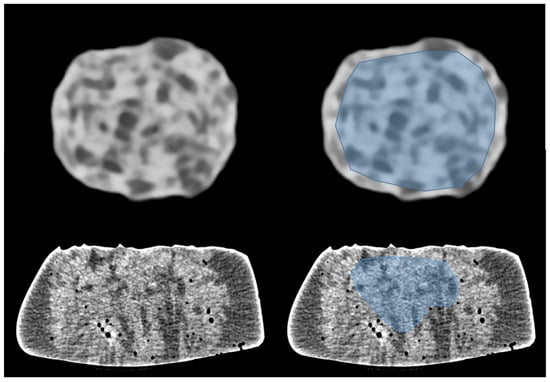

1. Introduction

2. Materials and Methods

2.1. Phantom Characteristics and Imaging Parameters

2.3. Radiomics Analysis